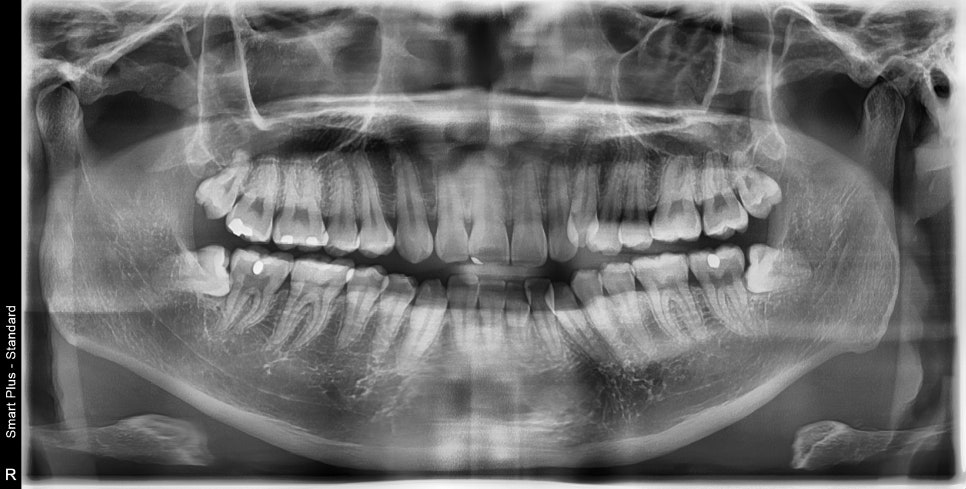

위 2개는 3일전에 발치, 아래 두개는 인비절라인을 시작하는 날 발치하고 바로 장치를 착용했습니다.

발치 교정으로 인비절라인 끝난 환자분으로

오른쪽은 그냥 돌출입의 교정

왼쪽은 덧니의 발치교정으로